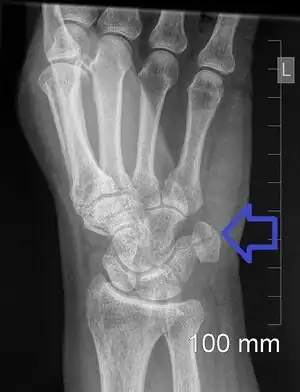

Pisiform fracture is a break of the pisiform bone of the wrist. Symptoms include wrist pain on the side with the little finger.[1][2] They may occur in association with other wrist bone fractures, injury to the ulnar nerve, or ulnar artery.[4][5] Complications may include arthritis and avascular necrosis.[1][3]

The cause is generally the wrist being directly hit, such as may occur during sports, falling on an outstretched hand, or from repetitive injuries.[1][5] It may also occur as an avulsion fracture.[1] Types are transverse, parasagittal, comminuted, and pisiform-triquetral impaction.[1] Diagnosis is generally by X-rays, though specific views may be required.[1] CT scan may be bone to rule out other injuries.[6]

The fracture may be better see on a specific wrist X-ray known as a carpal tunnel view or a lateral view with 30 degrees of supination.[4]